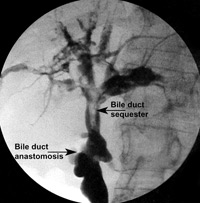

Η MRCP απεικονίζει με αρκετή ακρίβεια το χοληφόρο και παγκρεατικό δένδρο και

είναι εξέταση που προτιμάται σε παιδιά. Η ERCP είναι επεμβατική μέθοδος, προϋποθέτει

μεγάλη εμπειρία, ιδίως στην εφαρμογή της στα παιδιά και έχει αυξημένες πιθανότητες

επιπλοκών (αιμορραγίας ή παγκρεατίτιδας) (εικόνα 7).

EIKONA 7.

Πάγκρεας. MRCP. Κύστεις χοληδόχου και παγκρεατικού πόρου.

Πάγκρεας MRCP. Διάταση παγκρεατικού πόρου.

Πάγκρεας ERCP